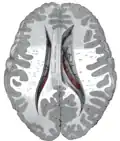

Anatomie

Samen met het putamen vormt de nucleus caudatus het striatum dorsale, dat functioneel als één structuur wordt gezien. Anatomisch gezien worden de twee gescheiden door een belangrijke baan van witte stof: de capsula interna. De nucleus caudatus bevindt zich in beide hersenhelften, aan de wand van de zijventrikels en schrijlings op de thalamus.[7] De boogvormige kern heeft een dikke kop en loopt steeds dunner uit in een soort staart, waaraan de structuur haar naam te danken heeft.